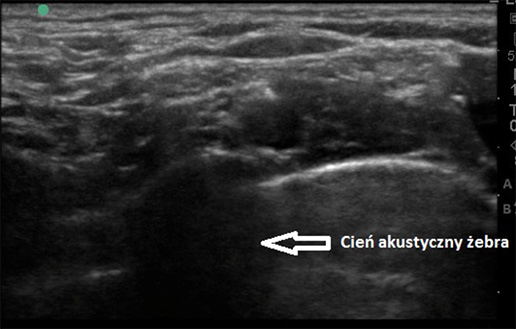

Ultrasonografia utożsamiana jest przede wszystkim z obrazowaniem obszarów wewnątrz pacjenta przy użyciu fal ultradźwiękowych. Skutkami niepożądanymi tej metody obrazowania jest punktowy wzrost temperatury oraz wytwarzanie, po przekroczeniu progu kawitacji, pęcherzyków gazów i wzrost ciśnienia w komórkach badanej tkanki. USG jest zatem kierunkowym przekazywaniem energii w tkance przy pomocy fali ultradźwiękowej, ogniskowanym w pewnym punkcie i odbiorem obrazu generowanego przez falę odbitą.…

Wprowadzenie Filozofią kontroli jakości jest poddawanie danego obiektu testom sprawdzającym jego funkcje i parametry, aby można było stwierdzić, że sprzęt pracuje prawidłowo i nie zagraża użytkownikom oraz osobom leczonym. Kontrolę jakości należy przeprowadzać według wytycznych. W Polsce takie wytyczne przewidziano m.in. dla aparatów rentgenowskich, mammografów czy tomografów komputerowych, jednak nie dla ultrasonografów, mimo że dostęp do tego badania…